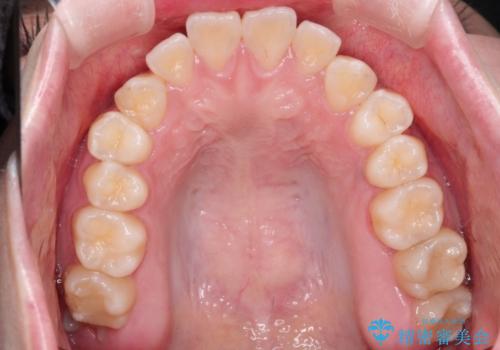

【インビザライン】歯を抜かずにできるだけ前歯を下げたい

- 前歯の前突を主訴に来院されました。

インビザライン を用いて、歯並びの改善を行うことができました。